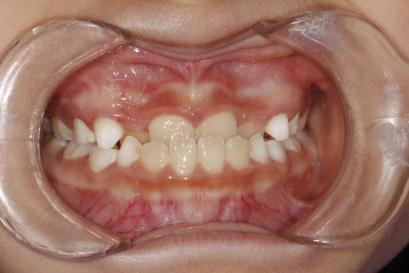

你见过这样的牙齿吗?这些就是典型的地包天。

地包天又称前牙反颌。是在乳牙期、混合牙期和恒牙期非常容易发生的一种牙齿畸形。正常的情况下,上颌的牙齿盖住下颌的牙齿。地包天反过来,下颌牙齿往前伸,下颌牙齿盖住上颌牙齿。

治疗前

治疗后